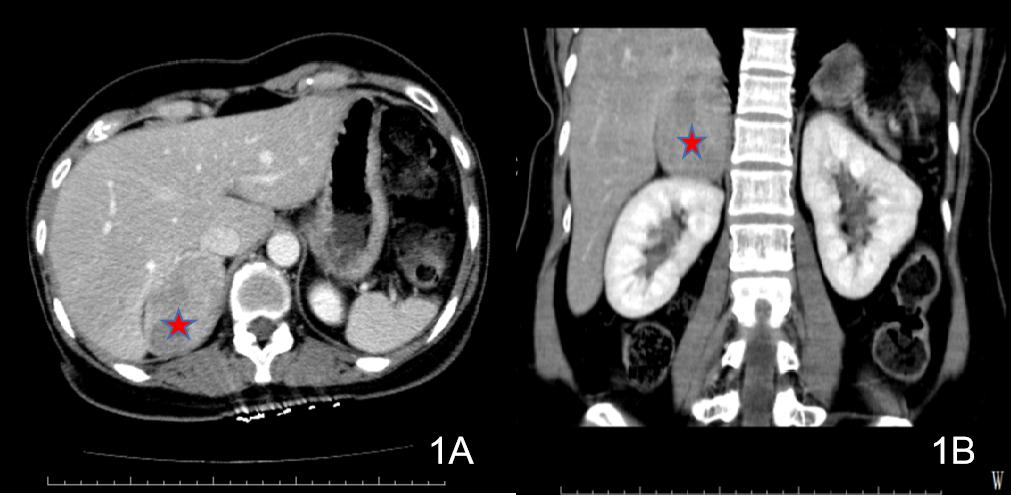

患者1初步诊断考虑急性暴发型病毒性心肌炎与儿茶酚胺心肌病鉴别,患者入院后心率快,呼吸促,满头大汗,面色苍白,双肺湿啰音,出现急性心力衰竭、肺水肿表现,病情进展迅速,随时可能出现心源性休克、恶性心律失常甚至心脏骤停等不良事件,当天转入重症医学科进一步诊治。转入后予以氧疗、控制心室率、营养心肌、抗感染、抗病毒、抗炎、护胃抑酸等支持治疗,效果欠佳,有ECMO辅助指征。征得患者及家属同意,于2017-10-01凌晨行清醒状态局麻下VA-ECMO治疗,使用右侧股动静脉切开置管。使用VA-ECMO模式,初始转速3 000 r/min,血流量3.0 L/min左右,气流量3.0 L/min,氧浓度100%,患者气促逐步缓解,心率90次/min,血压115/82 mmHg,SPO2 100%,尿量约100 mL/h。术前肝素首剂为50 mg,术后维持量为4~6 mg/h,APTT 43.8~70.3 s,ACT 130~168 s,全身各部位无明显出血,膜肺无血栓形成,在ECMO支持期间,同时予抗感染、抗病毒(阿昔洛韦)、人免疫球蛋白、艾司洛尔控制心室率(后过渡至酒石酸美托洛尔片)、控制血压等治疗。2017-10-02心脏彩超示EF下降至16%,2017-10-04将EF恢复至48%,撤离VA-ECMO。2017-10-06心脏彩超:左室心尖运动稍减弱,主动脉瓣返流(轻),二、三尖瓣返流(轻),左室射血分数57%,舒张功能稍减退。2017-10-10行冠脉造影未见明显异常。患者病情好转出院。2017-11-20返院复诊,查腹部CT发现右侧肾上腺区肿块,考虑嗜铬细胞瘤(见图 1),予服用“酚苄明”血压控制良好。2017-12-14复查心脏彩超提示:二、三尖瓣返流(轻度),左室收缩、舒张功能正常,EF 70%,肺动脉压正常(25 mmHg)。2017-12-15行择期手术治疗,病理结果符合嗜铬细胞瘤,术后患者血压恢复正常。患者最后诊断“嗜铬细胞瘤、儿茶酚胺心肌病”。

| 图 1 2017-11-20患者1腹部CT(右侧肾上腺区肿块) |